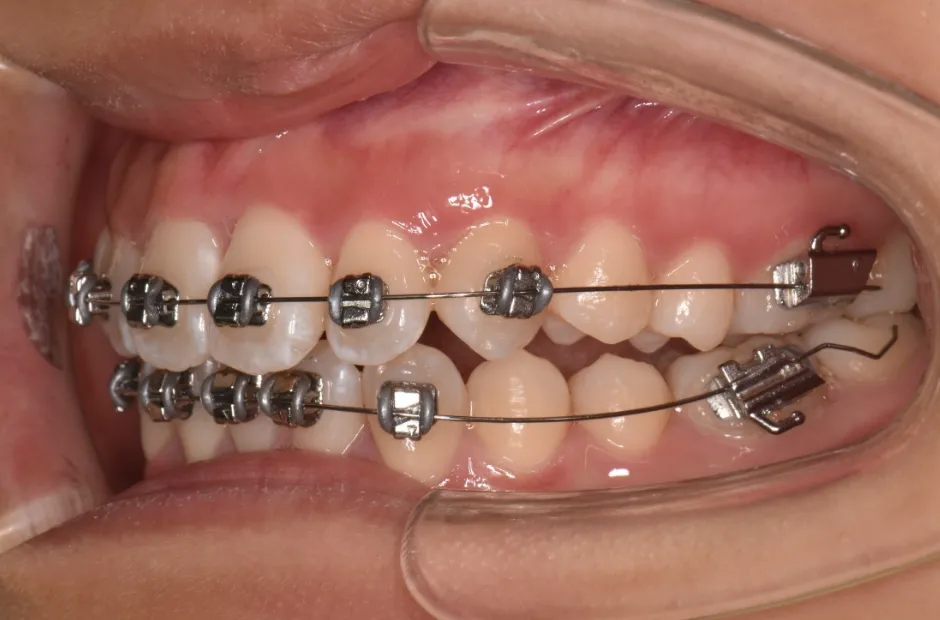

治療症例

ブラケット矯正

前歯部反対咬合

| 診断名・主訴 | 前歯部反対咬合 |

|---|---|

| 年齢・性別 | 14歳・男性 |

| 治療期間・回数 | 1年2か月 |

| 治療に用いた主な装置 | ブラケット矯正 |

| 抜歯部位 | なし |

| 治療費 | 60万円(税抜) |

| リスク・副作用 | 装置による違和感・疼痛・歯肉退縮・歯根吸収・虫歯のリスクなど |

治療前

治療中